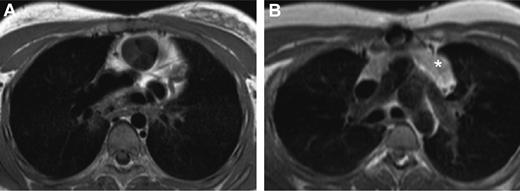

We investigated whether regrowth of thymic tissue could have been responsible for the generation of new TREC-containing naive T cells by analyzing MRI scans of the chest (Figure 3). These scans had been performed for clinical reasons in 8 patients from our study group (median age, 19.5 years; range, 3.9-28.8 years). Thymic tissue could be identified on scans from 6 of the 8 patients (Table 1). To further substantiate this finding, MRI scans from an additional group of 24 patients thymectomized during an arterial switch operation (median age at thymectomy, 0.03 years) were assessed to determine the presence of thymic tissue (median age, 9.6 years; range, 4.0-28.0 years). Combined with the MRI scans of the study group, a total of 48 scans from 32 patients were available. In 4 of the 32 patients, no thymic tissue could be observed. From one of these patients, a second scan was available that was made 2.5 years later and still showed no evidence of thymic tissue. In 7 individuals, thymic tissue was present but smaller than expected for the age of the individual. In one of these patients, the thymus size remained small on subsequent scans, whereas 5 of these patients eventually showed normal thymus sizes on subsequent scans. In 26 individuals, thymic tissue eventually reached a size comparable to age-matched healthy controls (Figure 4). Whenever thymic tissue could be identified on an MRI scan, any follow-up scans from the same individual always reconfirmed the evidence for thymic tissue. Whenever the size of the thymic tissue had become normal for the age of the individual, the thymus size on follow-up scans always remained normal.

Visualization of thymic tissue in thymectomized individuals. (A) MRI of a patient (T25) 10.6 years after thymectomy showing no evidence of thymic tissue. (B) MRI of a patient (T30) 16.5 years after neonatal thymectomy showing thymic tissue (*).